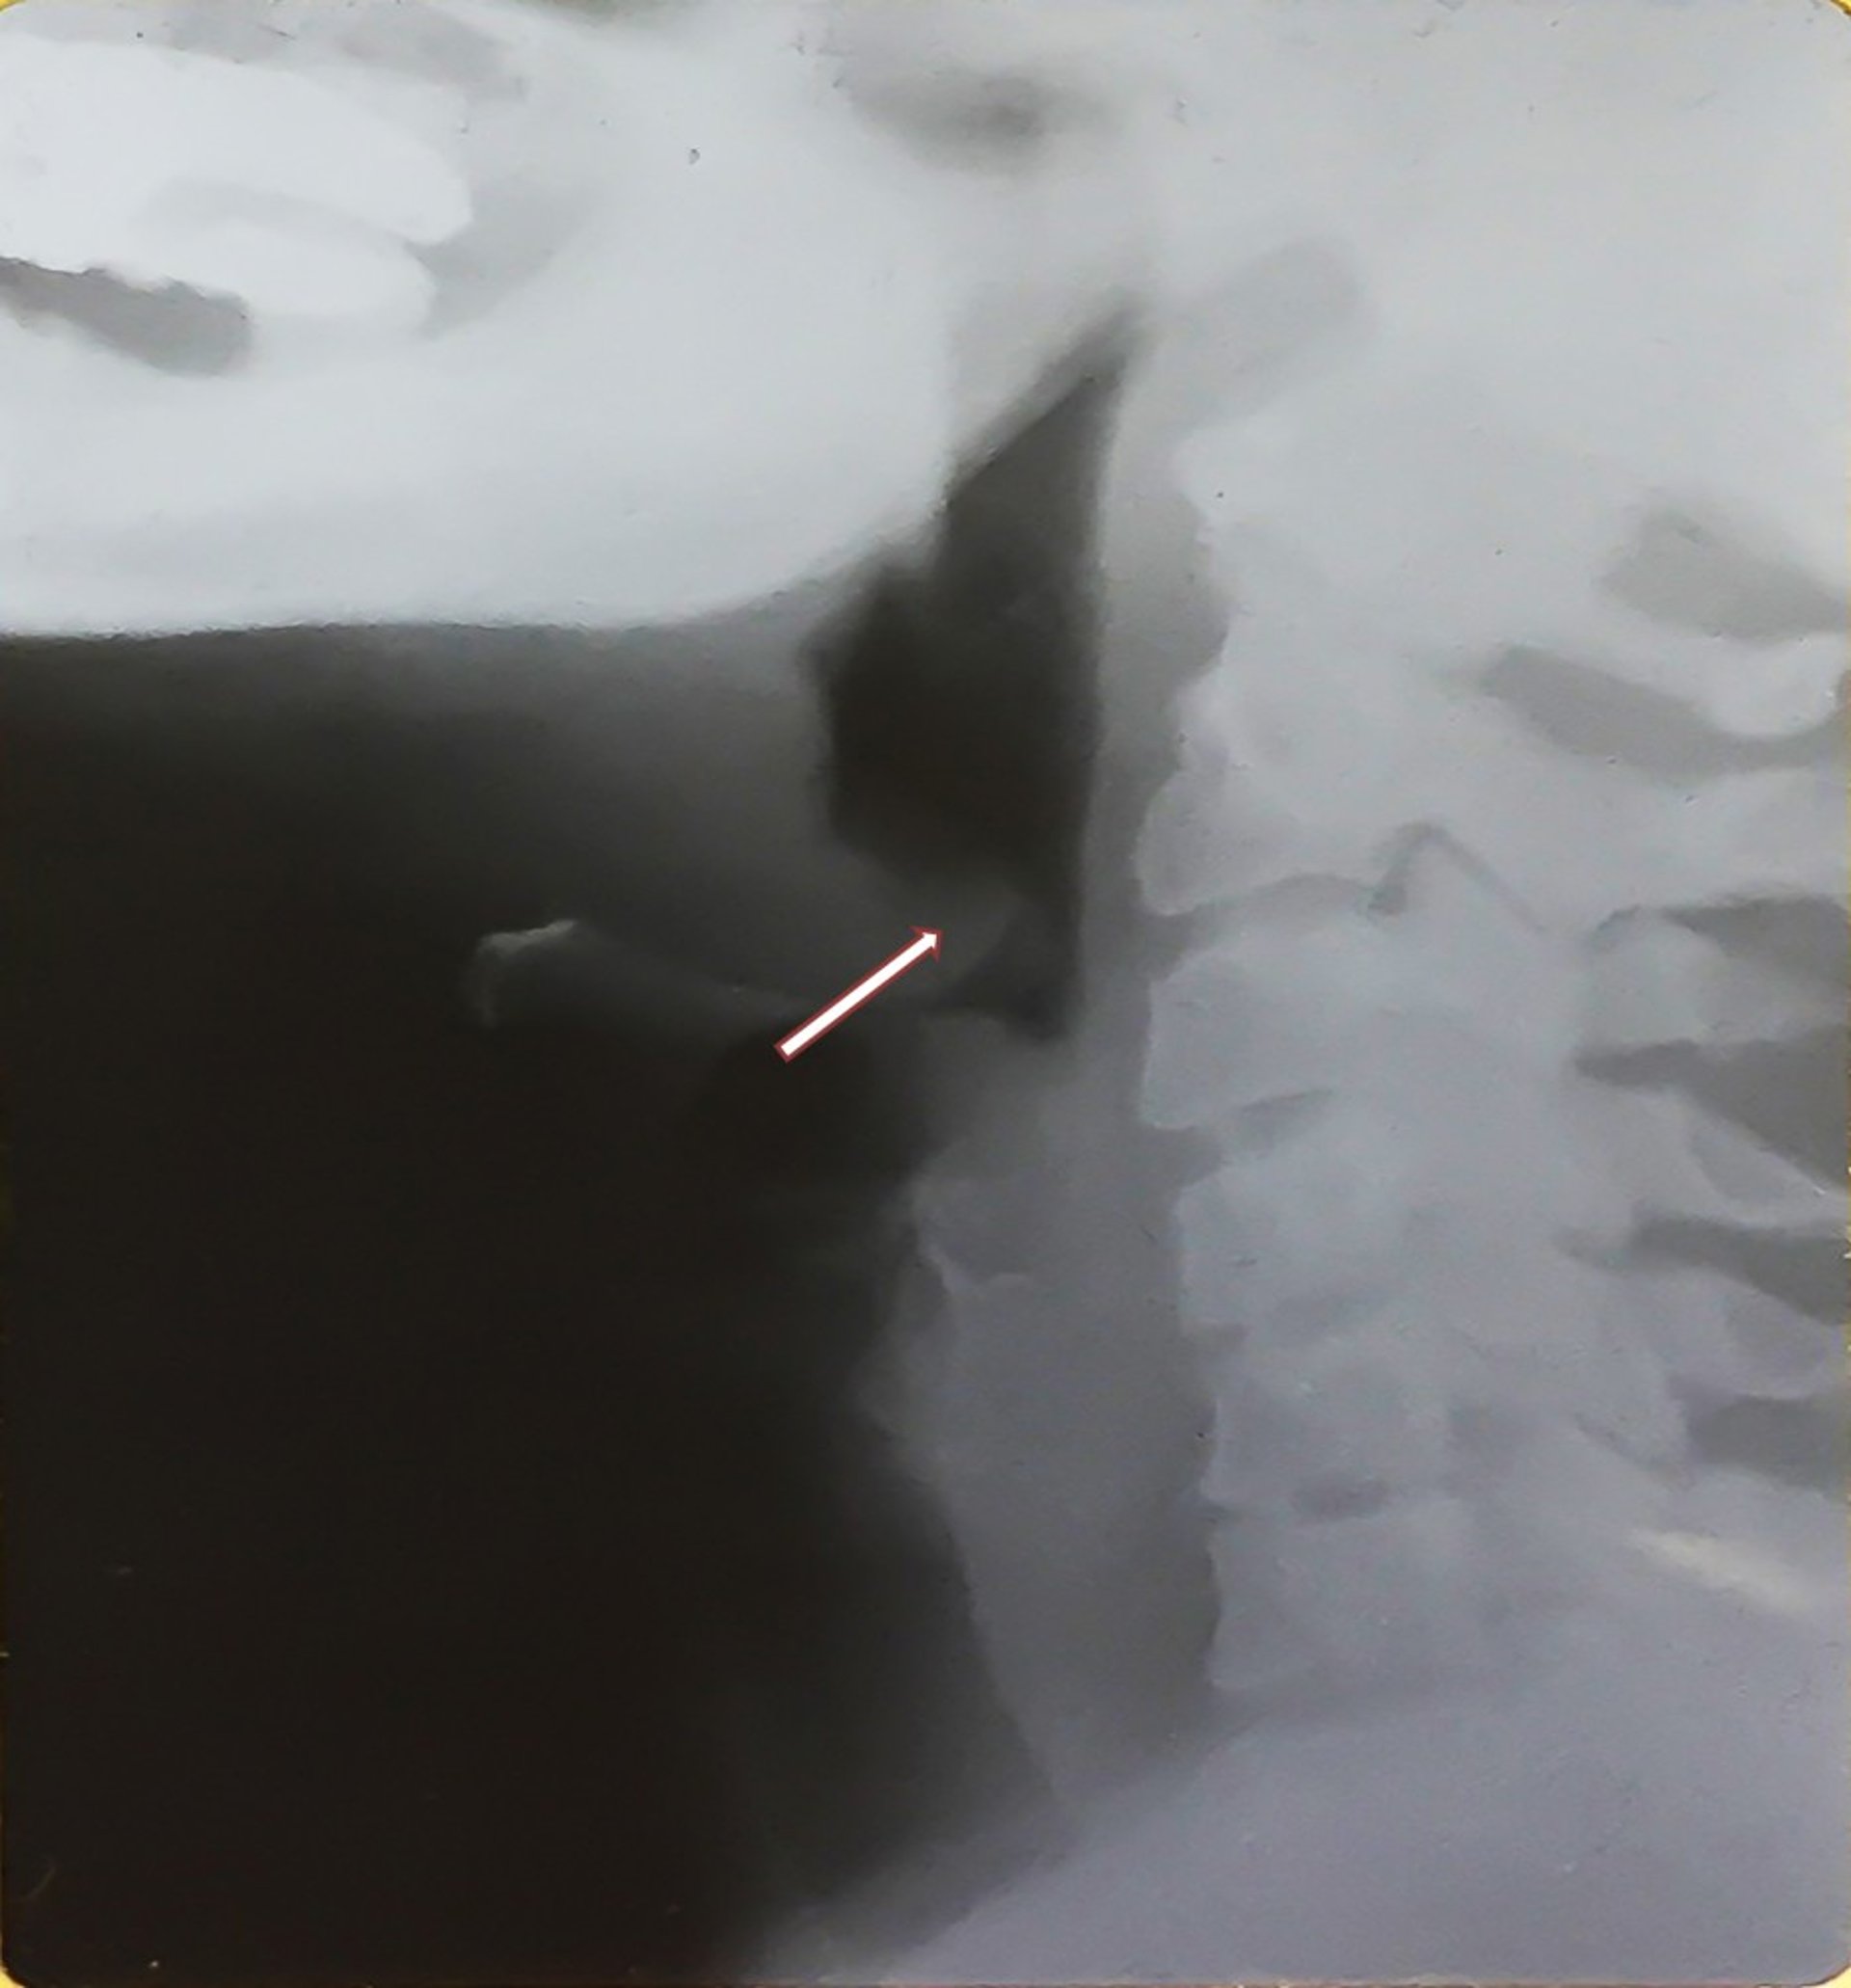

Epiglottitis (Adult)

This x-ray shows the enlarged epiglottis (thumb sign—see arrow) characteristic of epiglottitis and distention of the hypopharynx. Note the posteriorly displaced, thickened epiglottis.

Image provided by Clarence T. Sasaki, MD.